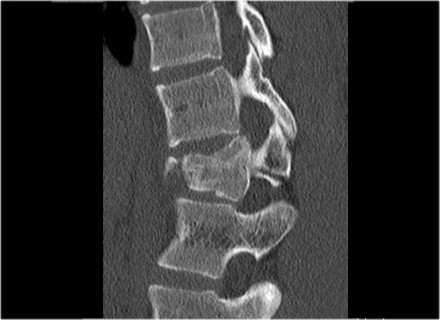

The images are of a patient with a typical bamboo spine as a result of ankylosing spondylitis.

After a fall on his back no fracture was seen on the x-rays.

However the CT shows a thin fracture line through the anterior side of the vertebral body and also through the spinous process.

Continue with the MR-images.

Look at the images.

What are the findings?

Then scroll to the next images.

The findings are:

- Vertebral bodies show marrow edema as a result of a fracture.

- Torn flaval ligament (yellow arrow).

- Fractures through the posterior elements (red arrows).

The TLICS-score is high, because there is distraction and injury to the PLC.